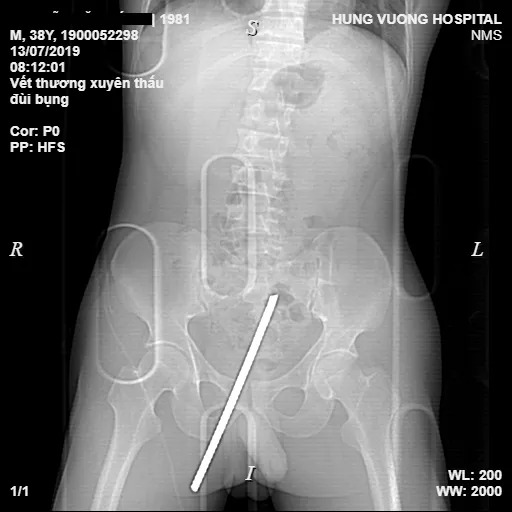

13/07/2019 22:55Nhảy từ trên xe xuống, thanh niên suýt bị thanh sắt 20 cm xuyên thấu 'của quý'

Ngày 13-7, Bệnh viện đa khoa Hùng Vương (Phú Thọ) cho biết khoảng 8 giờ sáng cùng ngày, các bác sĩ tại đây đã cấp cứu thành công nam bệnh nhân 38 tuổi (ở tỉnh Tuyên Quang) bị một thanh sắt dài khoảng 20 cm đâm xuyên thấu từ đùi phải lên bụng. Nam bệnh nhân được đưa vào Bệnh viện đa khoa Hùng Vương cấp cứu trong tình trạng đau đớn, mất vận động vùng đùi phải, dị vật xuyên thấu vùng đùi phải, sát gốc "của quý" lên vùng bụng và còn lộ đầu sắt dài khoảng 10 cm.

Người nhà cho biết bệnh nhân là lái xe chở vật liệu xây dựng, khi nhảy từ trên xe xuống đất đã không quan sát kỹ và bị thanh sắt cắm mốc dưới đất xuyên thẳng vào đùi. Ngay khi xảy ra tai nạn, các công nhân trong công trường đã dùng cưa sắt cưa đứt phần gốc thanh sắt và đưa nạn nhân đến Bệnh viện Hùng Vương cấp cứu.

Kết quả chụp chiếu cận lâm sàng của bệnh nhân cho thấy hình ảnh dị vật kim khí trong phần mềm dưới da vùng bẹn mu bên phải, sát dương vật, xuyên chéo lên đi dọc theo thành bụng dưới rốn trái.

Kíp mổ gồm các bác sĩ tim mạch, tiêu hóa, ngoại chấn thương và gây mê… đã hội chẩn, đánh giá sơ bộ về nguy cơ gây tổn thương ổ bụng do thanh sắt lớn gây ra cho bệnh nhân và chỉ định phẫu thuật xử lý vết thương. Sau 3 giờ đồng hồ phẫu thuật, các bác sĩ đã lấy dị vật ra khỏi cơ thể bệnh nhân. Bệnh nhân được chuyển phòng Hồi sức cấp cứu tiếp tục điều trị.